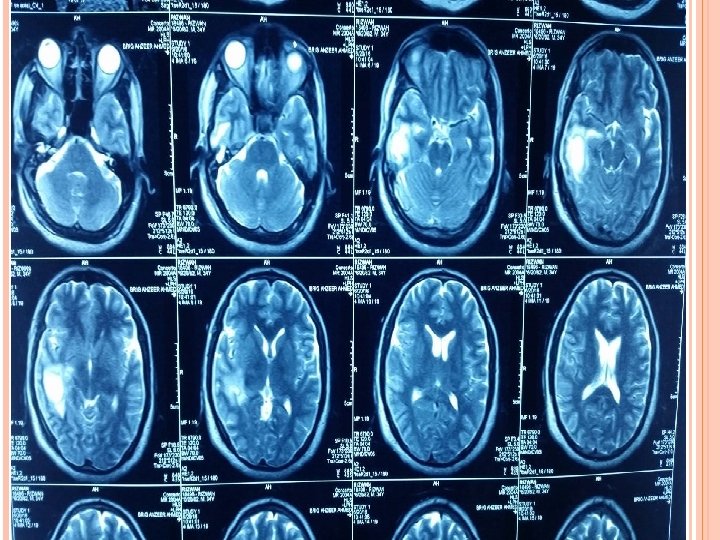

INVESTIGATIONS Blood Tests CBC (TLC-12000/u. L) CRP (3. 2 mg/L) ESR (28 mm/hr). Imaging CT scan Brain ( plain ) CT scan Brain with contrast. MRI Brain with contrast.

INVESTIGATIONS Radiological characteristic of brain abscess 1. Brain CT with contrast Ring enhancement Sigle Locus/Multi loculation Multiplicity Finding of gas

MRI T 1 : necrotic center ( hypointense) Capsule ( hyperintense) Edema ( hypointense) T 2 : necrotic center ( hyperintense) Capsule ( hypointense) Edema ( hyperintense)